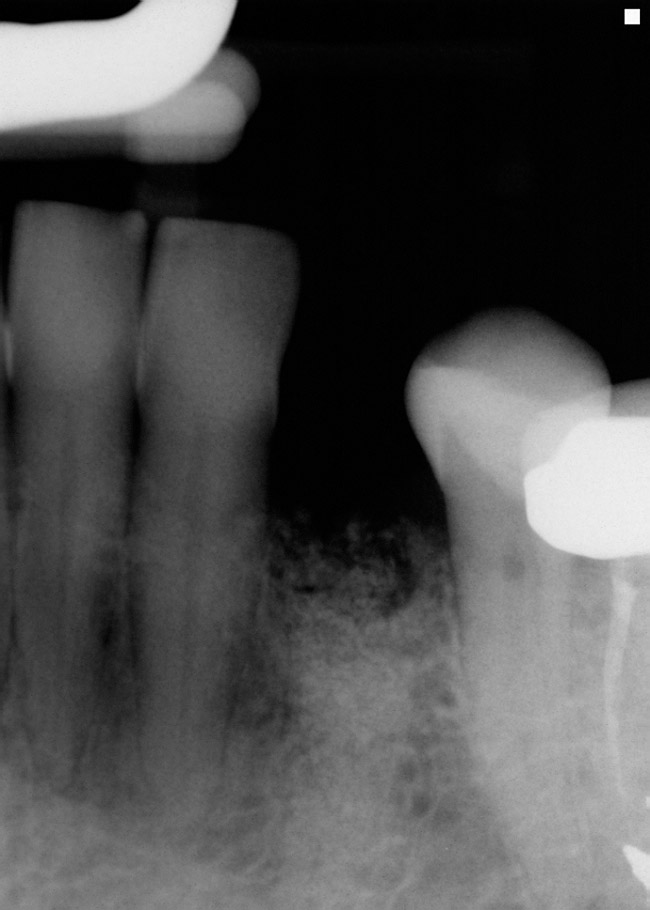

Din cele 109 implante inserate la cei 69 pacienţi în cursul unei perioade de 4 ani, nu s-a înregistrat niciun eşec implantologic după inserţia dispozitivelor fixe şi restaurarea protetică ulterioară. La descoperirea implantelor, nu erau semne de mobilitate a acestora, şi toate implantele inserate au fost restaurate. În momentul prelucrării datelor, toate implantele au rămas complet încărcate şi în funcţiune, rezultând o rată de supravieţuire de 100% (tabelul 1). Ca şi grup, implantele erau funcţionale şi încărcate de o perioadă medie de 2 ani, variind între 6-65 luni. Indiferent de tipul implantului, localizarea în alveolă, statusul de fumător, 100% din implante sunt în funcţiune şi actualmente (tabelul 1 şi fig. 1-9).